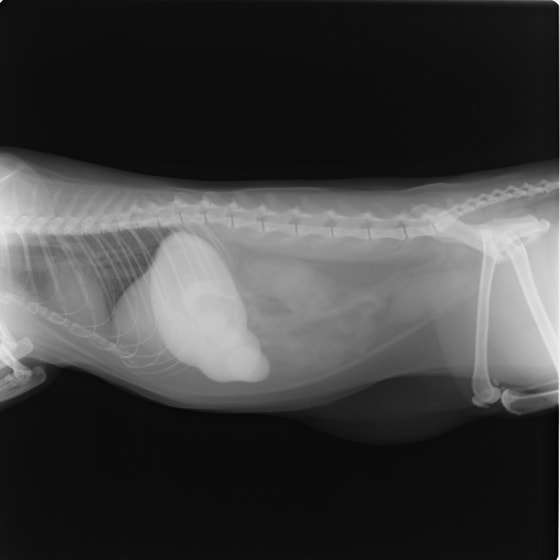

9歳 チワワ 4.8kg

主訴:2日前の夜に桃の種を飲み込んだとのこと。元気・食欲に問題はなく、嘔吐などの消化器症状もみられなかった。誤飲した当日に他院にて催吐処置を試みたが、吐き戻さなかったとのこと。

単純レントゲン検査:明らかな異常所見なし

消化管バリウム造影レントゲン検査:胃内にて異物の存在を疑う異常所見を認めた。

造影直後

内視鏡検査:内視鏡下にて、バスケット鉗子を用いて胃内異物を摘出。

異物内容:桃の種 (約4cm大 写真上)、とうもろこしの芯 (約2.5cm大 写真下)

本症例は、床に落としてしまった桃の種を誤飲していました。動物の体格に対して異物が非常に大きく、開腹手術となる可能性があった症例でした。また、桃の種と一緒に出てきたとうもろこしの芯は、日々のおやつとして与えていたものということでした。とうもろこしの芯は非常に硬く、小さく切って与えても消化されず、長期間胃内に残ってしまうことや腸閉塞の原因となる為、注意が必要です。